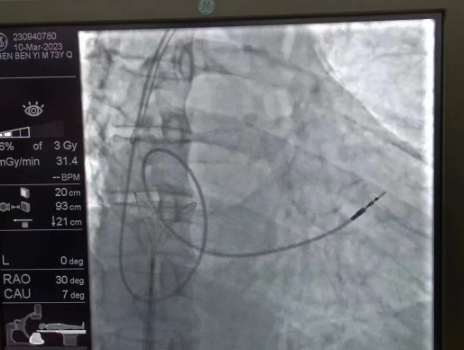

術(shù)中,孫書紅醫(yī)師首先切開起搏器囊袋,游離出起搏器脈沖發(fā)生器,發(fā)現(xiàn)起搏電極完全斷裂,連接于起搏脈沖發(fā)生器,殘端約10cm;考慮患者為起搏依賴患者,需再次植入新的起搏電極導(dǎo)線,穿刺了腋靜脈,放置導(dǎo)絲;同時(shí),李偉杰教授穿刺了左、右股靜脈,于右股靜脈置入了”抓捕器”,左股靜脈備用臨時(shí)起搏通路,以防術(shù)中出現(xiàn)心跳驟停。為了準(zhǔn)確抓捕到心房?jī)?nèi)的在逃起搏電極,李偉杰教授將導(dǎo)管室的X光機(jī)球管調(diào)整成了冠脈模式,這就意味著在抓捕過程中,醫(yī)生要比平時(shí)的手術(shù)“吃”更多射線……

在透視模式下,抓捕全憑醫(yī)生的經(jīng)驗(yàn)與手感,一次次嘗試,一次次失敗,在場(chǎng)外觀摩手術(shù)的醫(yī)生同樣為李偉杰教授捏了一把汗,“找到了!”電子屏里抓捕器向在逃起搏電極“發(fā)起進(jìn)攻”,一把逮住并順利拔出一根長(zhǎng)達(dá)58cm的起搏電極。